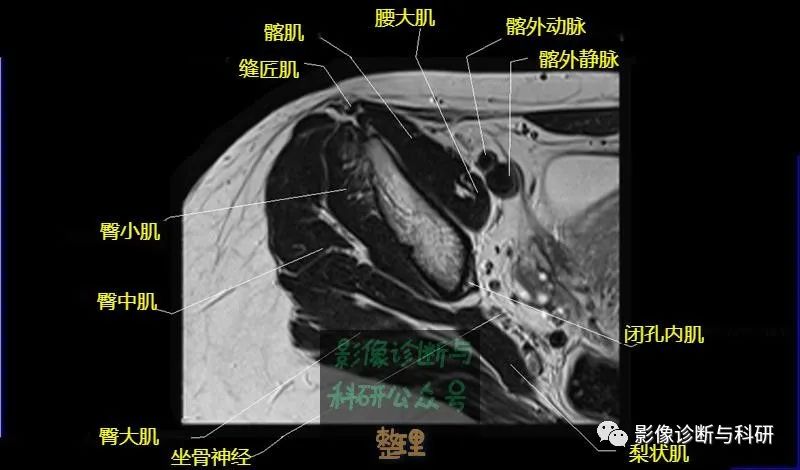

髋关节MR轴位详细标注